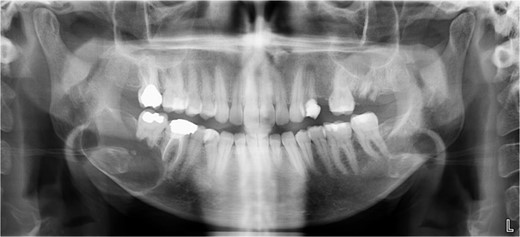

A 40-year-old woman presented with swelling on the right side of her mandible. She had completed orthodontic treatment 2 years earlier. A panoramic radiograph showed a unilocular radiolucency extending from the mandibular angle to the right first molar region (Figs 1–3).

Panoramic radiograph highlighting the extent of the lesion from the mandibular angle to tooth #46.